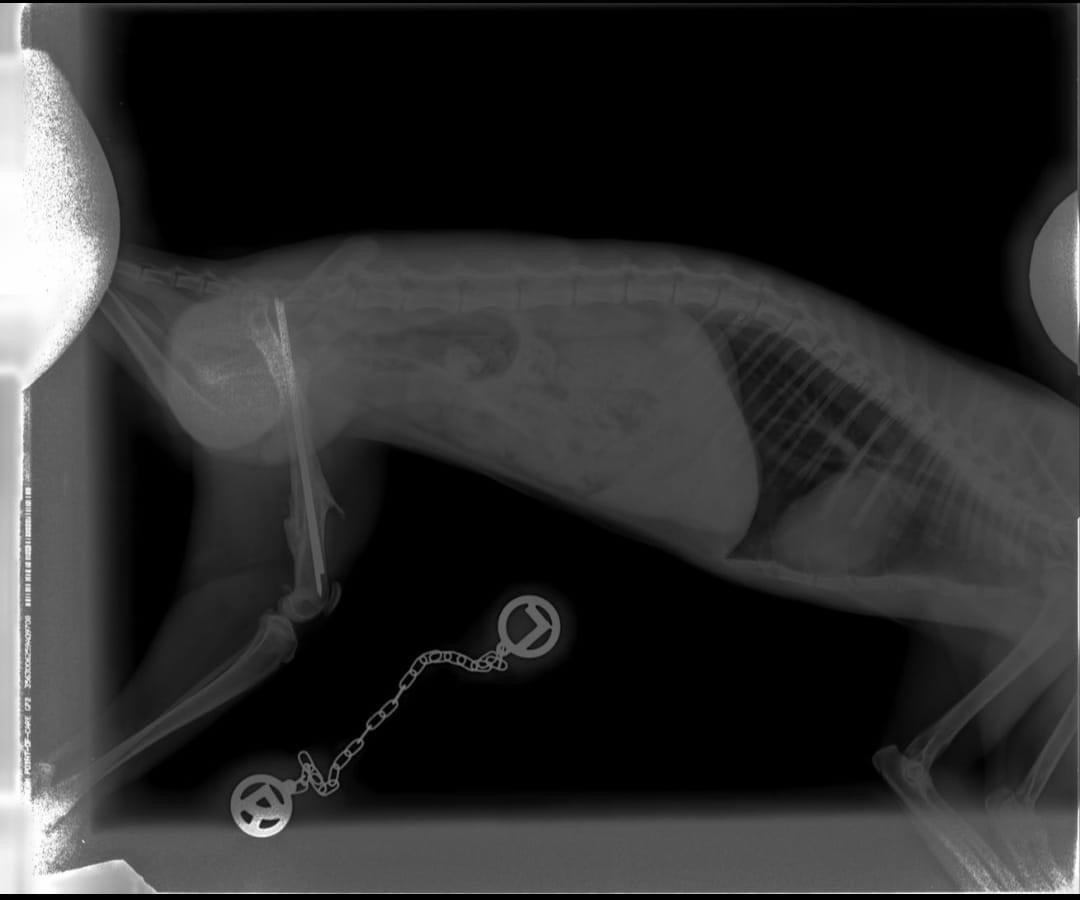

17.02.2023: Der Tierarzt der den kleinen Kater (ca. ein dreiviertel Jahr alt) in seine Praxis mitgenommen hat, hat erstmal versucht ihn wieder zu wärmen und so seine Temperatur zu erhöhen. Er wurde dann geröntgt und hat alle notwendigen Medikamente bekommen. Dabei konnte man einen zersplitterten Bruch erkennen der durch diese viel zu lange Osteosynthese (Stabilisierung des Knochens) zusammengehalten wird. Diese OP muss erst vor kurzem gemacht worden sein. Vor ca. 3 bis 4 Wochen. Der Stab der dort verwendet wurde ist jedoch viel zu lang, ragt aus dem Knochen raus und hat daher zu so einer unglaublichen Entzündung der gesamten Wunde geführt.

21.02.2023: Heute Vormittag hatten wir einen Termin in Wittstock bei den Hoftierärzten. Da wurde der Kasper als erstes noch mal geröntgt, um noch einmal zu schauen wie es jetzt in seinem Beinchen aussieht. Nach der Auswertung dieser Bilder wurde uns gesagt, daß die zwei Pins im Anschluss gezogen werden können. Die leichte Sedierung, die der Kasper zum röntgen bekommen hatte, wurde dann vertieft um die anstehende OP durchzuführen.

Während der OP wurden ihm die beiden Pins gezogen, das wilde Fleisch abgetragen und die Wunde sauber vernäht. Jetzt muss Kasper erstmal 2 Wochen ruhig bleiben, bevor die Fäden gezogen werden können.